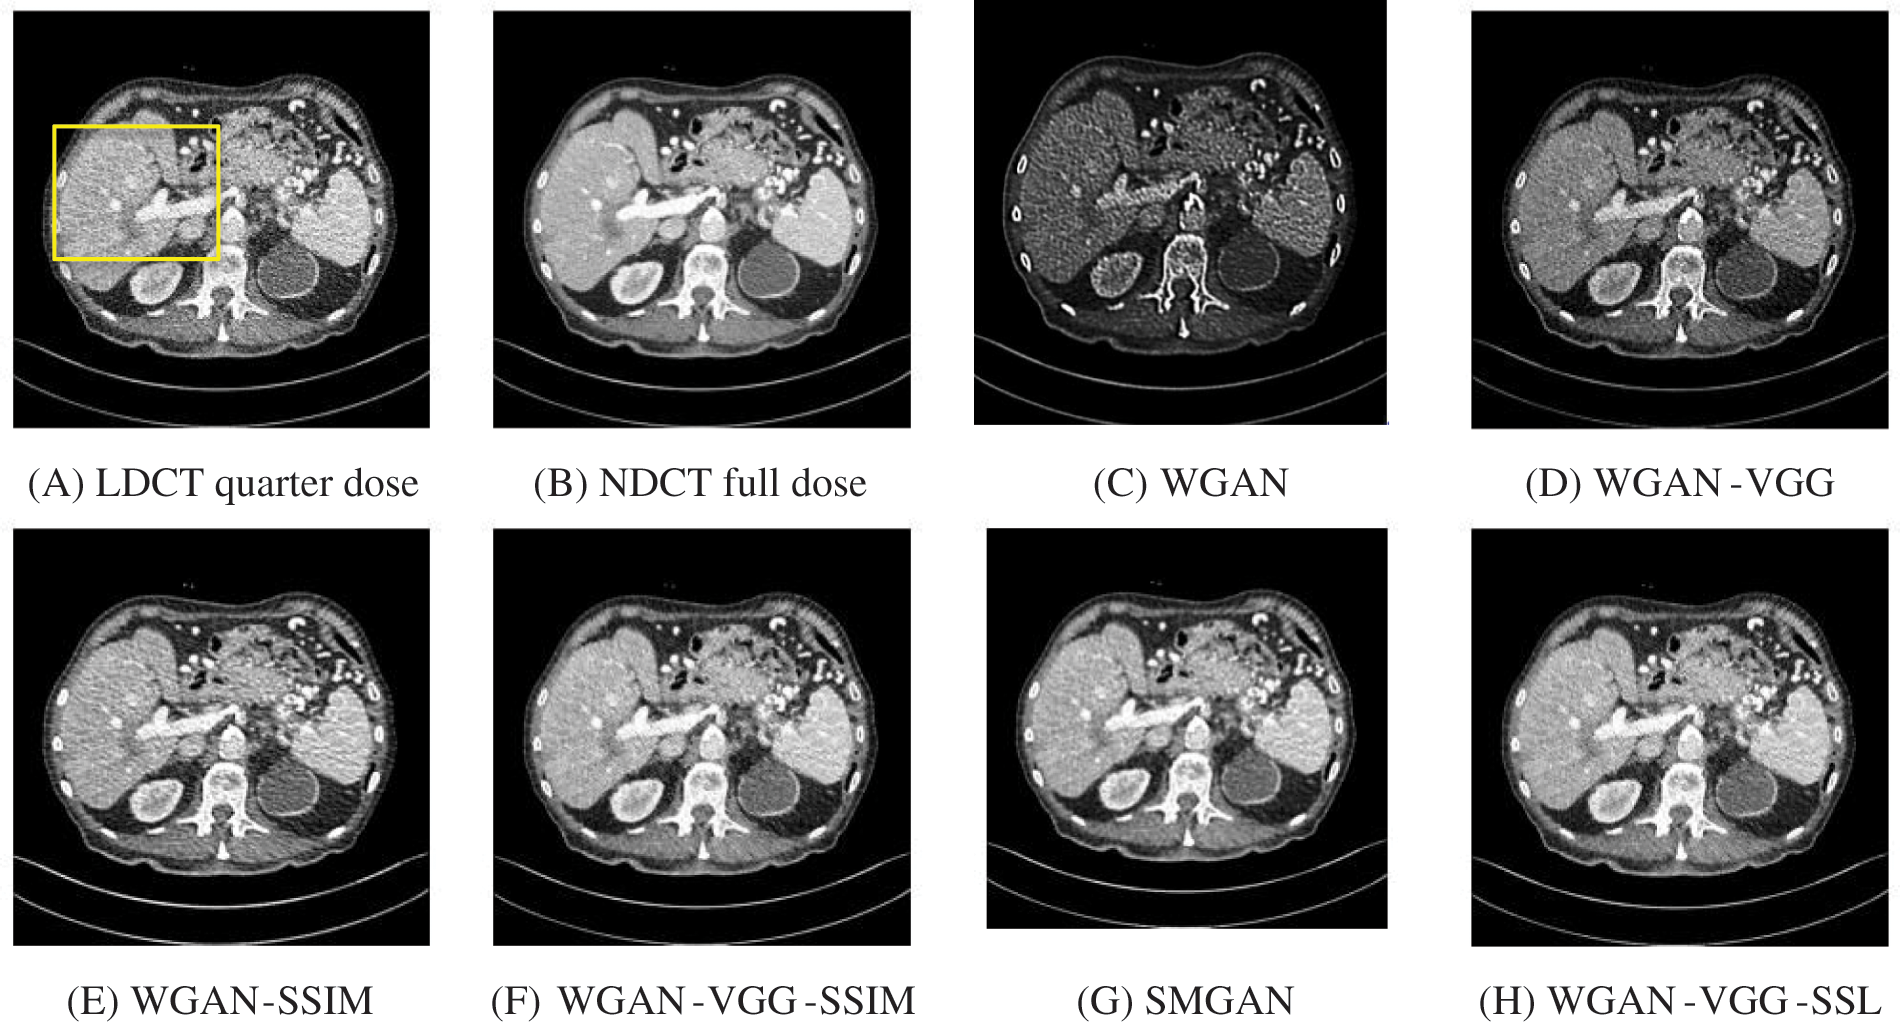

To assess the efficiency of the variant loss function, this work trained the proposed models (WGAN-SSIM, WGAN-VGG-SSIM, WGAN-VGG-SSL), and also trained the best-known models such as WGAN [30], WGAN-VGG [14], and SMGAN [25]. We used two examples of a CT image that were taken from the testing data folders ‘L067’ and ‘L506’, and took a zoomed representative slice of each example to show more structure details as a yellow rectangle in Figs. 2 and 3, and Figs. 6 and 7 respectively. The experimental results showed that generated images using WGAN have a more blurred appearance than the other models. Even though WGAN reduced the white artifact, the produced images are not considerably enhanced compared to NDCT images; some structures are over-smoothed, as shown in Fig. 7C with a red arrow. WGAN cannot preserve the edge details as shown in Figs. 2C and 3C, in which generated images lost the textures of the liver. WGAN-VGG has a few white structures. Although it produced images that were sharper than WGAN, it distorted some of the fine structure details. WGAN-VGG has low contrast as shown in Figs. 2D, 3D, and 7D with a yellow arrow; the performance of WGAN has not improved because it just moves from the noise distribution to the free distribution and does not depend on any human perceptual knowledge. On the other hand, perceptual loss is included in WGAN-VGG. WGAN-SSIM achieved visually better than WGAN and WGAN-VGG and preserved features as marked by the yellow arrow in Figs. 6E and 7E. It is noticed that the three models (WGAN-VGG-SSL, SMGAN, and WGAN-VGG-SSIM) preserved the fine image and retained informative details as shown in Figs. 6F–6H, and 7F–7H by red and yellow arrows. Finally, WGAN-VGG-SSL suppressed noise and artifacts, and generated images that are close to NDCT images; it also kept the structural features better than the other methods and determined the lesion location as pointed out by the red dashed circle in Fig. 6H. In conclusion, WGAN-VGG-SSL achieved better informative feature preservations and visual quality than other WGAN methods.

The time taken on the GPU was 20 times less than that on the CPU. The results of the experiment were taken on GPU after one hour of training. We used two examples of a CT image that were taken from the testing data folders ‘L067’ and ‘L506’, and took a zoomed representative slice of each example to show more structure details as a yellow rectangle in Figs. 4 and 5, and Figs. 8 and 9 respectively. At the beginning of learning, the WGAN model visually had poor informative structures and lost some details about the image, and the generated images were distorted with low contrast. That’s because of the very short training time. The resulting image using the WGAN-VGG preserved some of its characteristics, lost some other details, reduced contrast, and removed the streak artifacts better than WGAN as shown in Figs. 4D, 5D, and 8D by red and yellow arrows. The generated images from WGAN-SSIM preserved some informative details, but they still suffer from white structures. The generated images of WGAN-VGG-SSIM, SMGAN, and WGAN-VGG-SSL preserved more informative features as shown in Figs. 8F–8H, and 9F–9H by red and yellow arrows. They also kept the structural features better than the other methods and determined the lesion location as pointed out by the red circle in Figs. 8F–8H. WGAN-VGG-SSL reduced white structures and artifacts better than SMGAN and WGAN-VGG-SSIM; and produced images similar to NDCT images. The reason why WGAN-VGG-SSL achieved better informative feature preservations and visual quality than other WGAN methods, is that WGAN-VGG-SSL can balance between

Figure 4: The generated images from the testing data ‘L067’ on GPU at 2000 iterations

Figure 5: The generated images from the testing data ‘L506’ on GPU at 2000 iterations